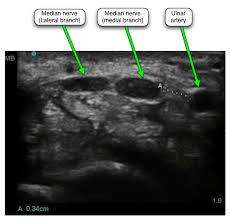

Ultrasound Guided Corticosteroid Injection In Carpal Tunnel Syndrome Jpr